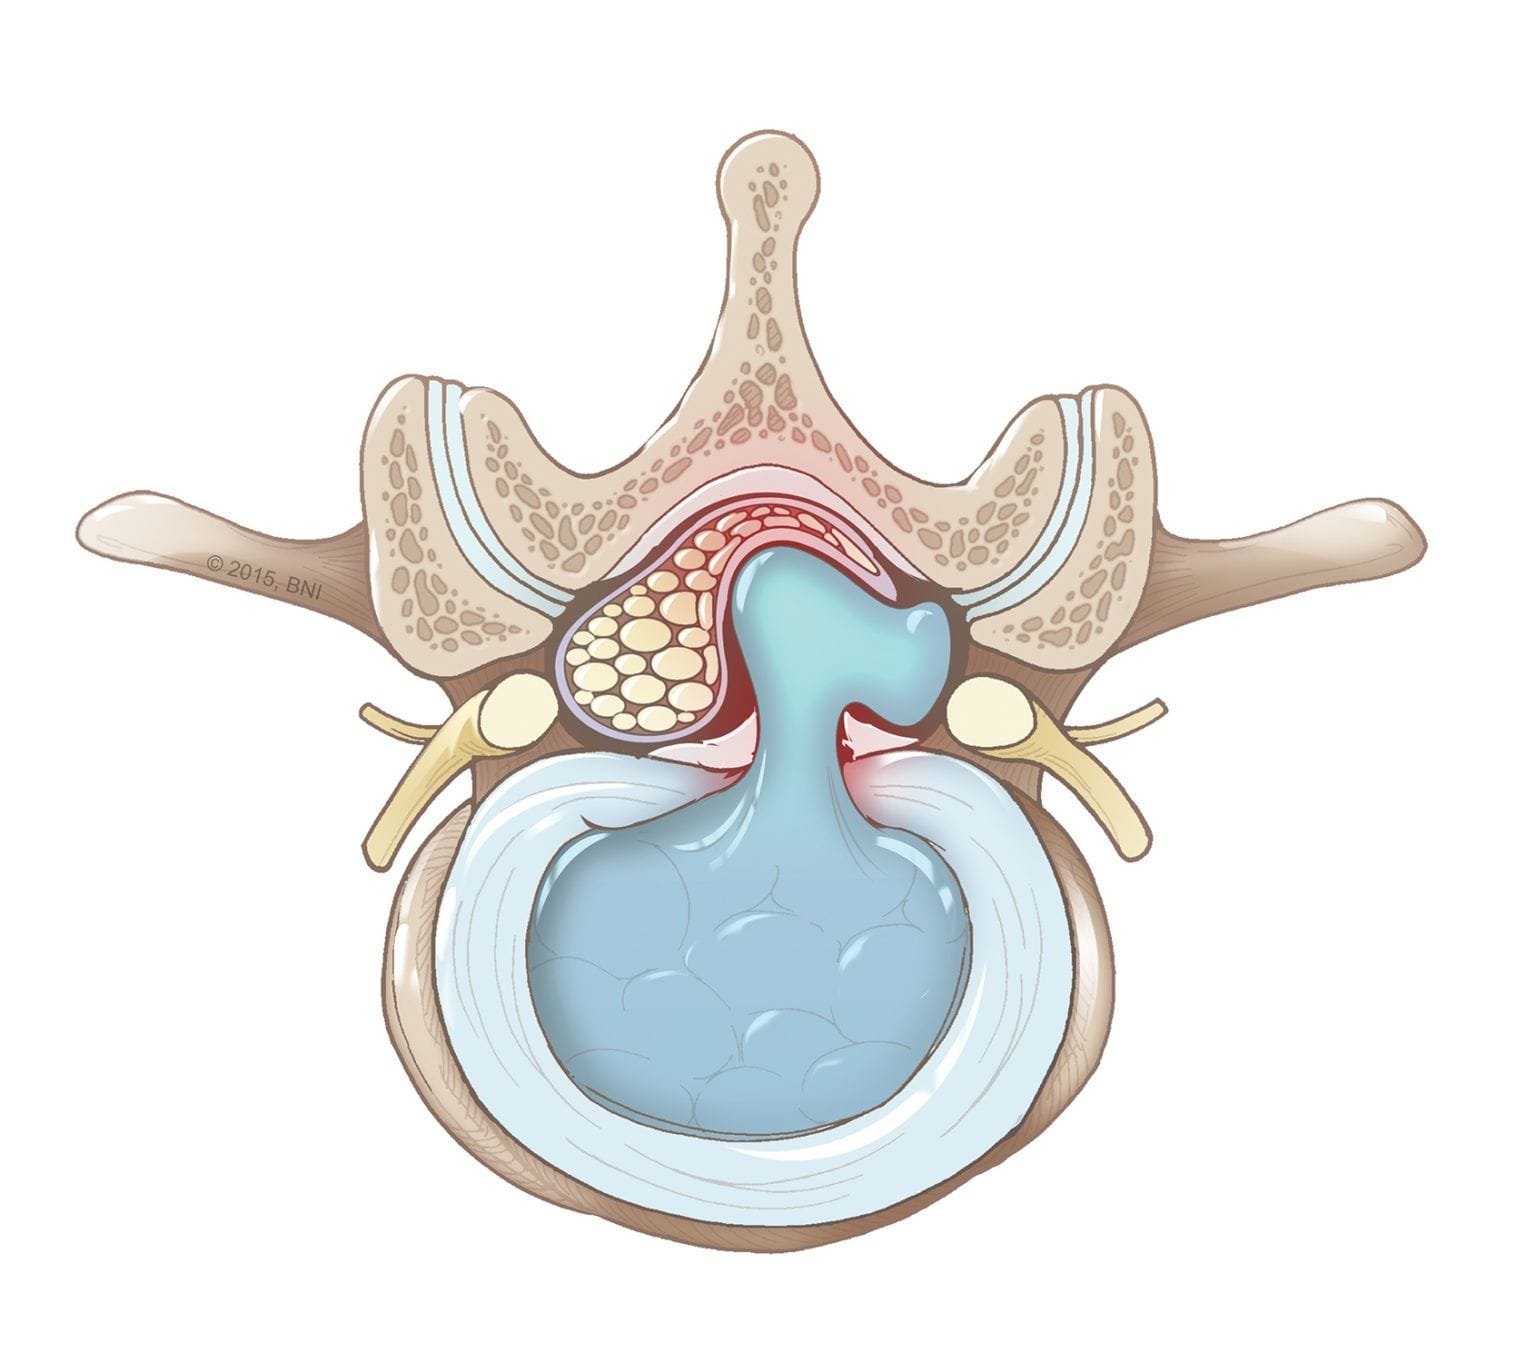

Protrusión discal

Es el abombamiento de las fibras periféricas del disco (anillo fibroso) hacia el canal por el que discurren las raíces nerviosas.

Hernia discal

El anillo fibroso se rompe y parte del núcleo pulposo se desplaza hacia el canal espinal.

Extrusión discal

Sucede cuando una gran cantidad del material del núcleo pulposo sobresale fuera del disco, pero sigue conectado por un fino tallo.

Migración discal

Es una hernia que se desplaza por encima o debajo de los límites del espacio interdiscal.

Cada una de estas lesiones tiene un impacto distinto en la columna y puede requerir diferentes tratamientos según la gravedad.